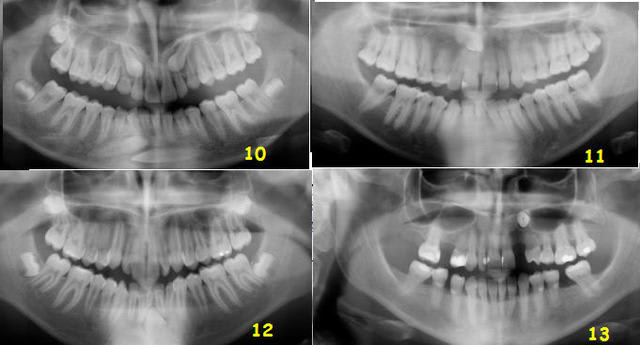

Et les autres, de 10 à 13 ?

Test canines suite et fin ljwpc0 - Eugenol

12: 33 L

13: couronne en V et apex en L ( si c'est l'inverse... c'est vraiment pas gagné )

pour les autres je ne suis pas encore décidée!!!

10: vestivulaires...toutes!!!

12: linguale

hum hum... et la n°11 ?

couronnne en mésio vestibulaire et apex en disto lingual...j'ai bon m'sieur???

4 sur 7.

C'est pas mal, c'est plus que la moyenne.

Qui dit mieux ?